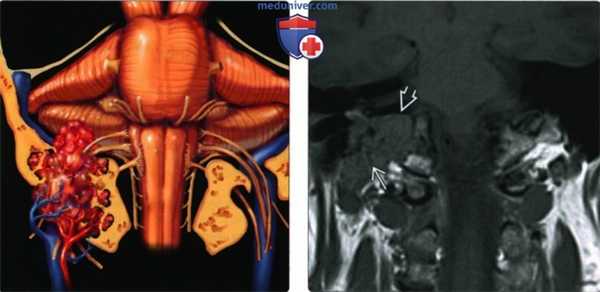

(Слева) На рисунке коронального среза показана крупная менингиома яремного отверстия, прорастающая в среднее ухо, костный мозг основания черепа и внутренний слуховой проход. Обратите внимание, в яремном отверстии опухоль окружает черепные нервы (IX-XI пары).

(Справа) При МРТ Т1 ВИ FS с КУ в корональной проекции определяется крупная менингиома яремного отверстия, прорастающая в костный мозг основания черепа. Для менингиом яремного отверстия характерен центрифугальный вектор распространения, часто они разрастаются вдоль поверхности твердой мозговой оболочки и сквозь окружающие кости.